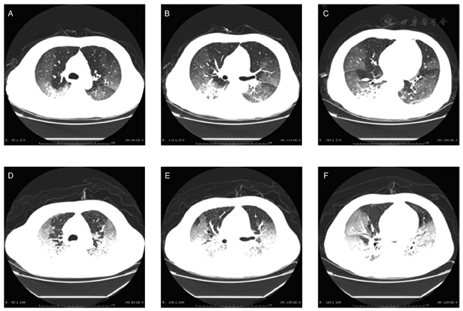

For example, the images in Figure 3 are from a patient who was treated with 40 mg methylprednisolone intravenously (iv) every day (qd) after admission. On day 6 of treatment, review of the lung computed tomography (CT) scan showed significant lesion progression and the patient ultimately died, indicating that lung changes caused by the 2019-nCoV were not inhibited by corticosteroid as was expected.